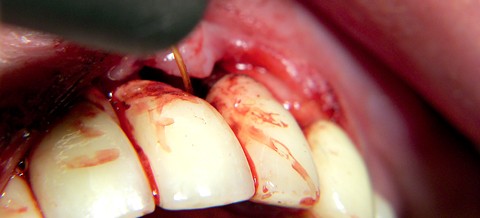

Typische Anwendung eines Diodenlasers – die Therapie der Periimplantitis.  Abb. 1: Bleeding on Probing an einem vor sechs Jahren incorporierten Implantat in der Oberkieferfront. Abb. 2: Auch das Röntgenbild zeigt typische Manifestationen einer Periimplantitis, einen kraterförmigen Knocheneinbruch.

Abb. 3: Bei der Mobilisation der Weichteile wird das ganze Ausmaß der knöchernen Destruktion sichtbar.  Abb. 4: Diodenlaserdekontamination: unter Kontakt der Faser zur freiliegenden Implantatoberfläche mit einer Leistung von 1 Watt im cw-mode wird das Laserlicht maximal 20 Sekunden appliziert.  Abb. 5: Postoperativer Nahtverschluss.